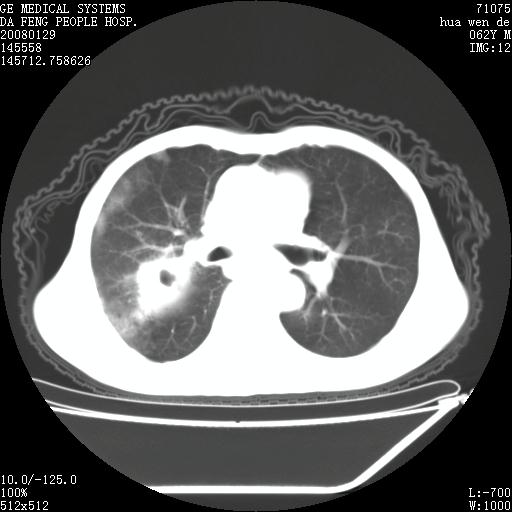

男性,67岁。作肺部检查时发现

1.整个食管扩张,未见明显占位性病变,贲门区亦未见明显占位病变,考虑:贲门失驰缓症;

2.右上肺病变边缘可见毛刺,囊壁厚度不均匀,周围境界较清楚,未见炎性渗出性影,右上肺外带可见片状影,边缘不清,考虑:肺癌伴空洞形成、右上肺炎。

肺内病灶位于右肺中叶,食道扩张后导致咽部功能受影响,吸入气管可能是存在的。

可疑之处在于:左肺未见吸入性病灶存在。另右肺癌(右肺中央型并阻塞性肺炎)不能除外

食管全程扩张,壁均匀不厚,喷门失弛缓症

右上肺空洞可见液平,临近肺野磨玻璃密度,考虑1.结核2.脓肿

贲门失驰缓症.肺部感染伴脓肿形成。支持!是否吸入性要结合临床诊断,我们影像是看不出来的。但胸腔胃能排除(1.没有手术史支持,2.双侧胸廓对称,胸壁、肋骨及胸膜规整,3,食管壁明显扩张内壁光滑,胸腔胃黏膜皱襞多较厚)。

右上肺空洞可见液平,临近肺野磨玻璃密度,考虑1.结核2.脓肿 支持!